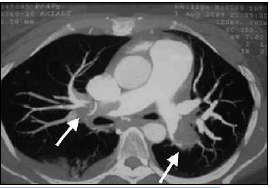

Observe a angiotomografia a seguir, que apresenta achados radiográficos assinalados por setas:

Assinale a hipótese mais provável para os achados da imagem anterior.